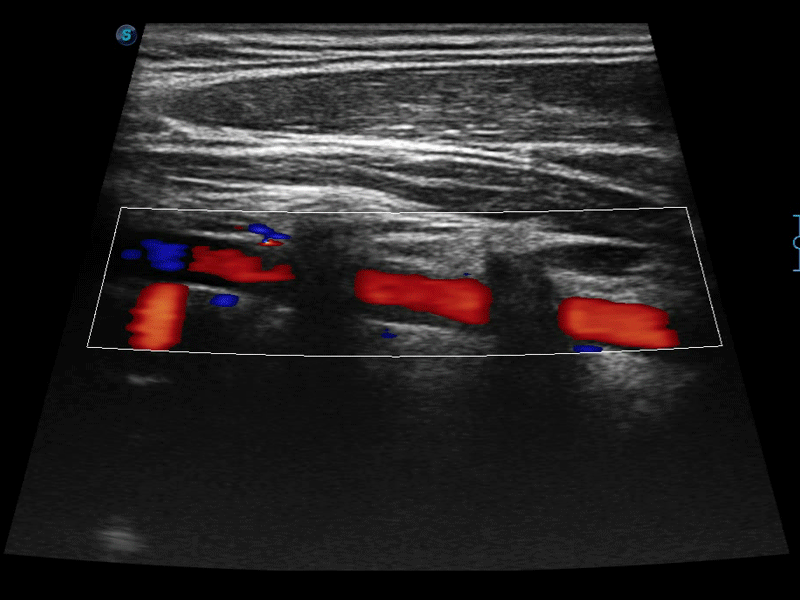

凸陣、線陣和相控陣探頭進(jìn)行實(shí)時(shí)掃描時(shí),開啟擴(kuò)展成像模式,可以擴(kuò)展超聲圖像視野,以便更完整地查看大的病灶或組織器官的解剖結(jié)構(gòu)。

通過色彩血流和實(shí)時(shí)寬景相結(jié)合,可觀察到完整的靜脈或動(dòng)脈的血流,方便醫(yī)生檢查。實(shí)時(shí)掃查過程中,如有任何操作失誤也可以很容易地進(jìn)行回掃擦除,而不會(huì)中斷掃查。